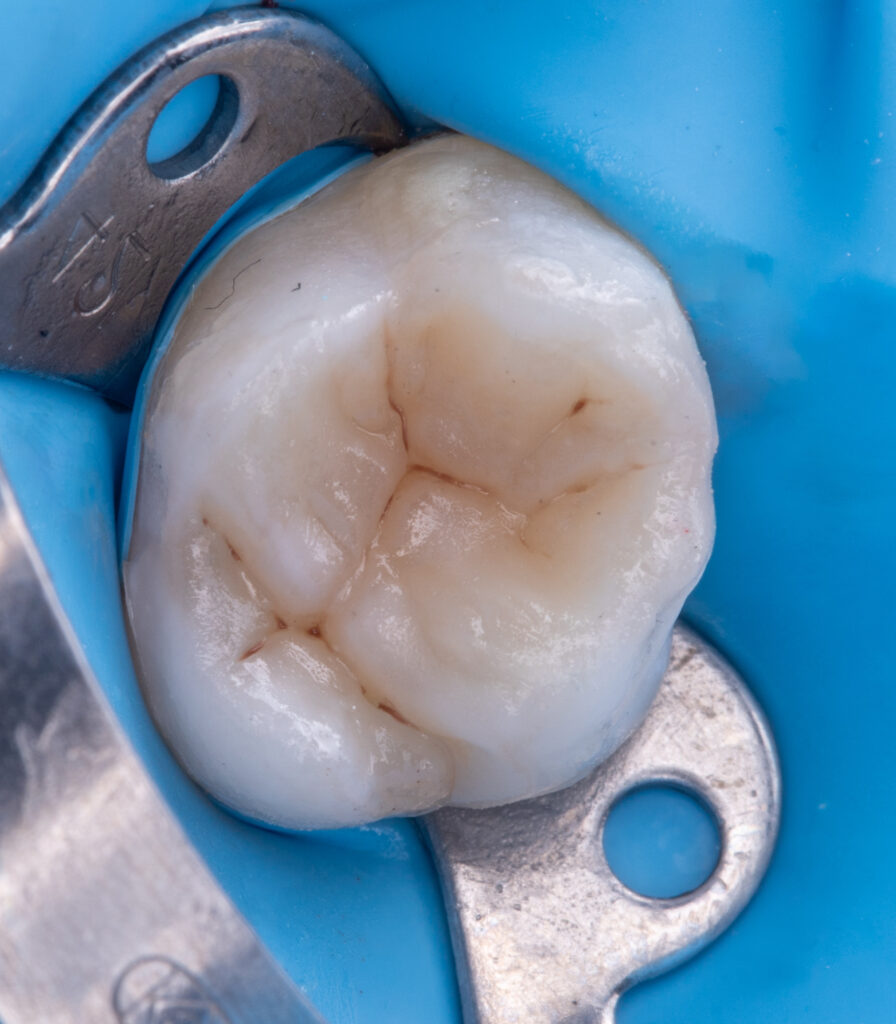

In a single visit, the old composite restoration was completely removed and replaced with a new composite (Asteria A2B / NeoSpectra A2).

EverX (flowable glass fiber composite) was used as a reinforcing layer to improve the strength and durability of the tooth.

Total treatment time: 50 minutes.